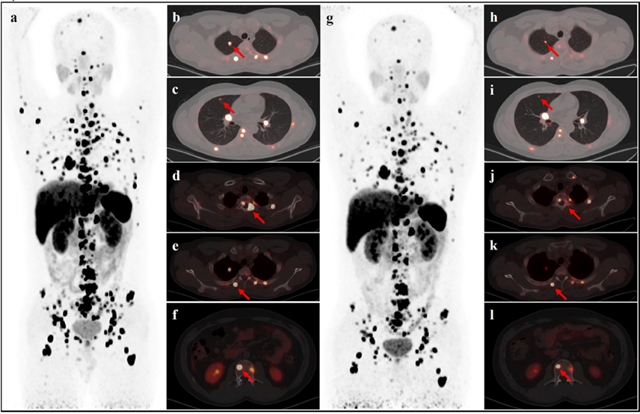

张春银:一位26岁的男性患者,7年前被诊断出患有嗜铬细胞瘤,当时接受了手术治疗。最近,该患者的嗜铬细胞瘤复发并多发转移,传统的治疗方式已经完全无效。目前,患者在我院已接受225Ac治疗3个周期,病情已出现明显好转。

图:患者第一次治疗前(a-f)和最后一次治疗后(g-l)的68Ga-DOTATATE PET-CT图像